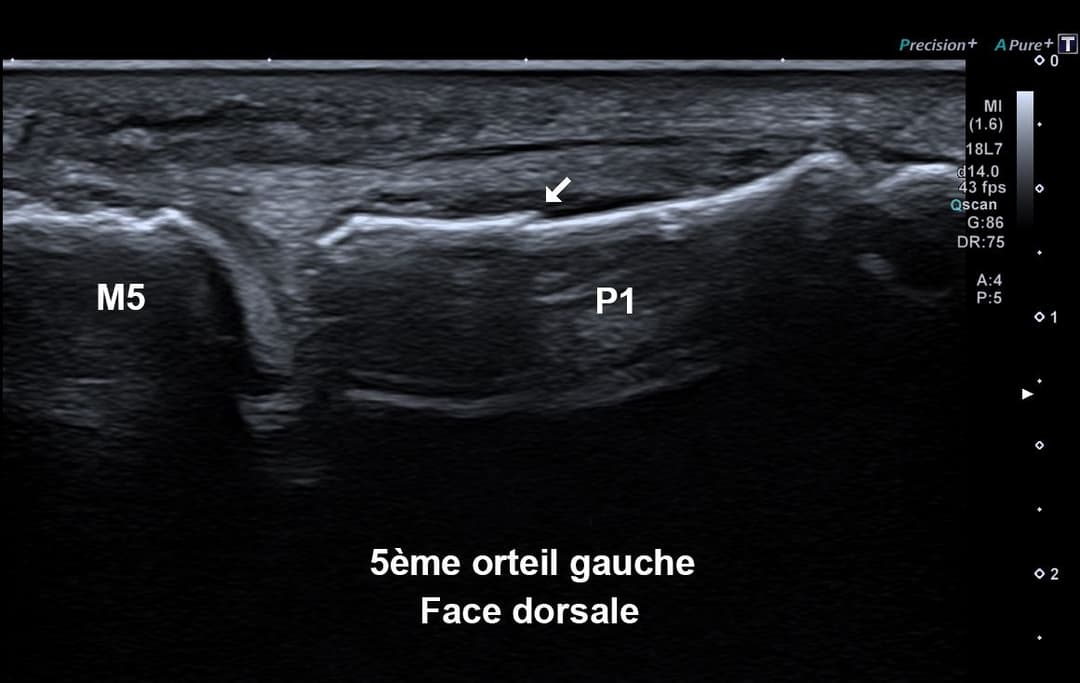

Douleur du 5ème orteil du pied gauche suite à un traumatisme par choc direct dans un meuble.

Échographie

Fracture instable étudiée en échographie dynamique